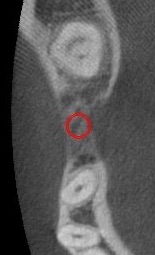

実際のシミュレーション時の画像です。

この赤く示されている部分にインプラントを埋めることを想定しています。

隣の歯との位置関係や角度に問題がないか確認します。

別の角度から見ています。

インプラントの下の方、骨の奥のところに黒く見えているのが血管や神経が通っている管です。

今回はインプラントの位置と距離があるので、安全に手術ができると予測されます。

また、骨の厚みなどから、どのような太さや長さのインプラントを埋めるか選んでシミュレーションしています。

次は上から見た時の位置予測です。

赤い円で示されているのがインプラントです。

ここしかないという部分にインプラントを埋める必要があります。

そのために事前に位置を確認して、シミュレーションしておくことが大事なのです。